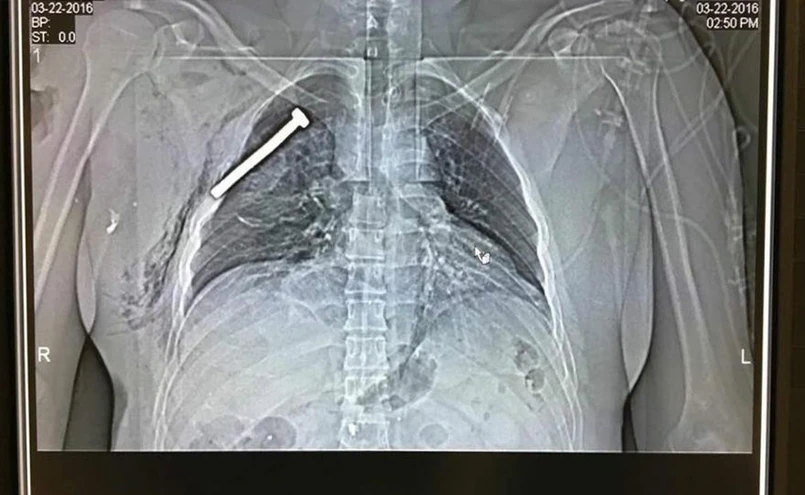

Zdjęcie rentgenowskie ofiary zamachów w Brukseli wykonane w wojskowym szpitalu w Neder-over-Heembeek. Na fotografii widać śrubę wbitą w klatkę piersiową rannego pacjenta

Zdjęcie rentgenowskie ofiary zamachów w Brukseli wykonane w wojskowym szpitalu w Neder-over-Heembeek. Na fotografii widać śrubę wbitą w klatkę piersiową rannego pacjenta/PAP/EPA

Lekarze z wojskowego szpitala w Neder-over-Heembeek położonego w północnej części Brukseli opublikowali fotografię rentgenowską klatki piersiowej pacjenta rannego w jednym z wtorkowych zamachów terrorystycznych w Brukseli. Na zdjęciu wyraźnie widać wbitą w ciało stalową śrubę. W porannych doniesieniach podawano również informacje o znajdowanych na miejscu zamachów stalowych gwoździach, którymi wypełnione były ładunki wybuchowe.